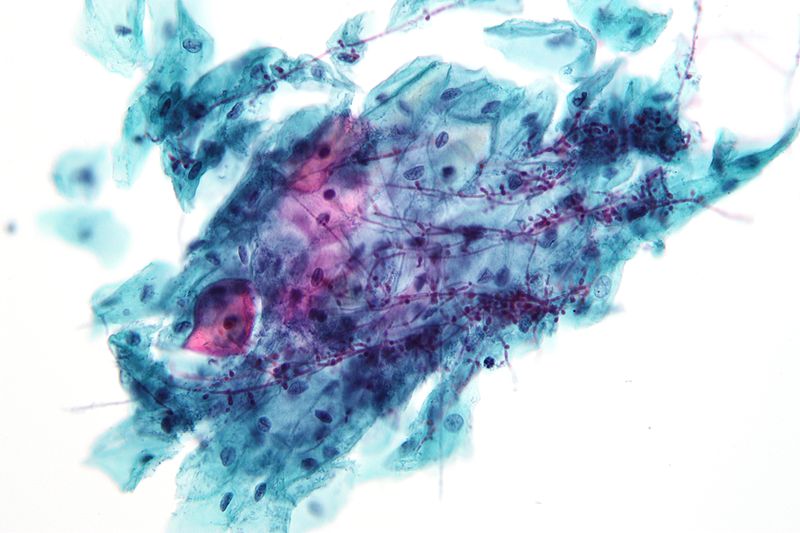

Blood Culture Yeast With Slide Blood Tests For Yeast Infection Blood cultures are a vital diagnostic test in detecting bloodstream infections. Your doctor will take your blood. Yeast is a type of fungus that lives on your skin and. In september 2014, the fda gave marketing approval for the t2candida panel and t2dx instrument (t2candida), the first direct blood. The most common test for invasive candidiasis is a blood culture. Blood Tests For Yeast Infection.